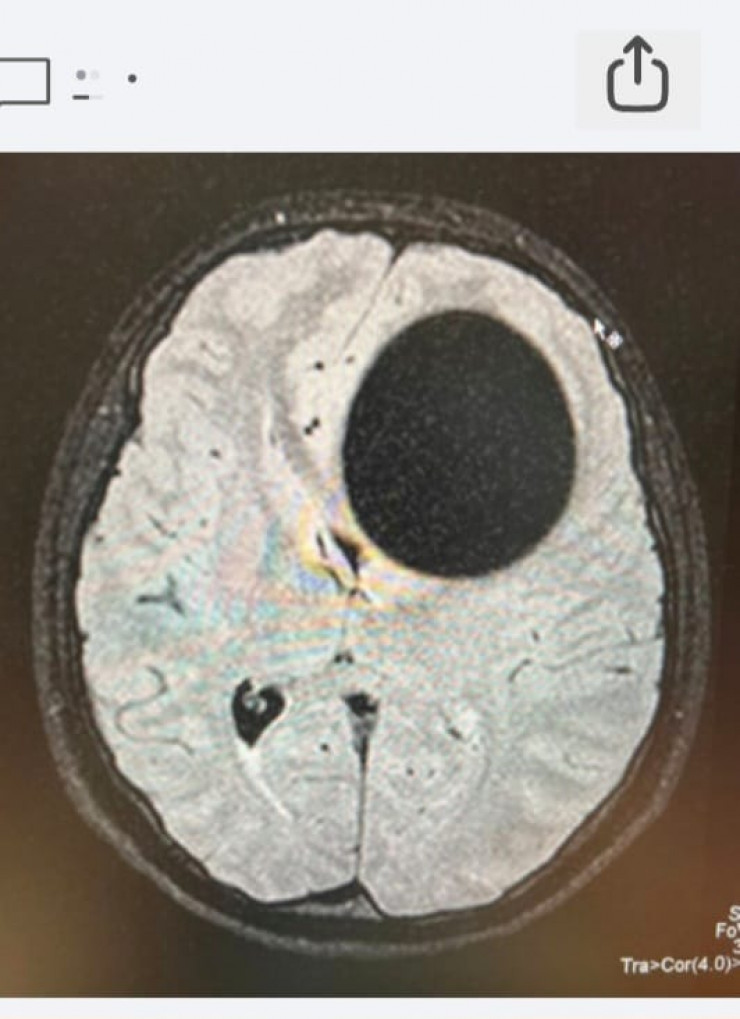

КТ-снимок до операции.